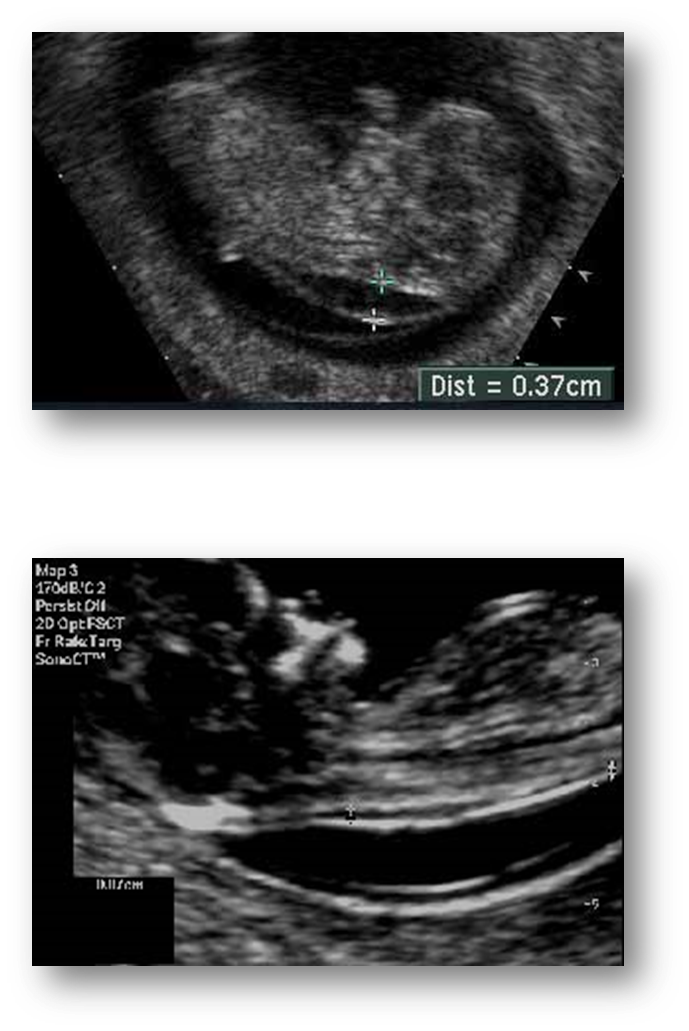

What are these images showing?

Midface Hypoplasia or Maxillary Hypoplasia

What is this image showing?

Absent nasal bone What